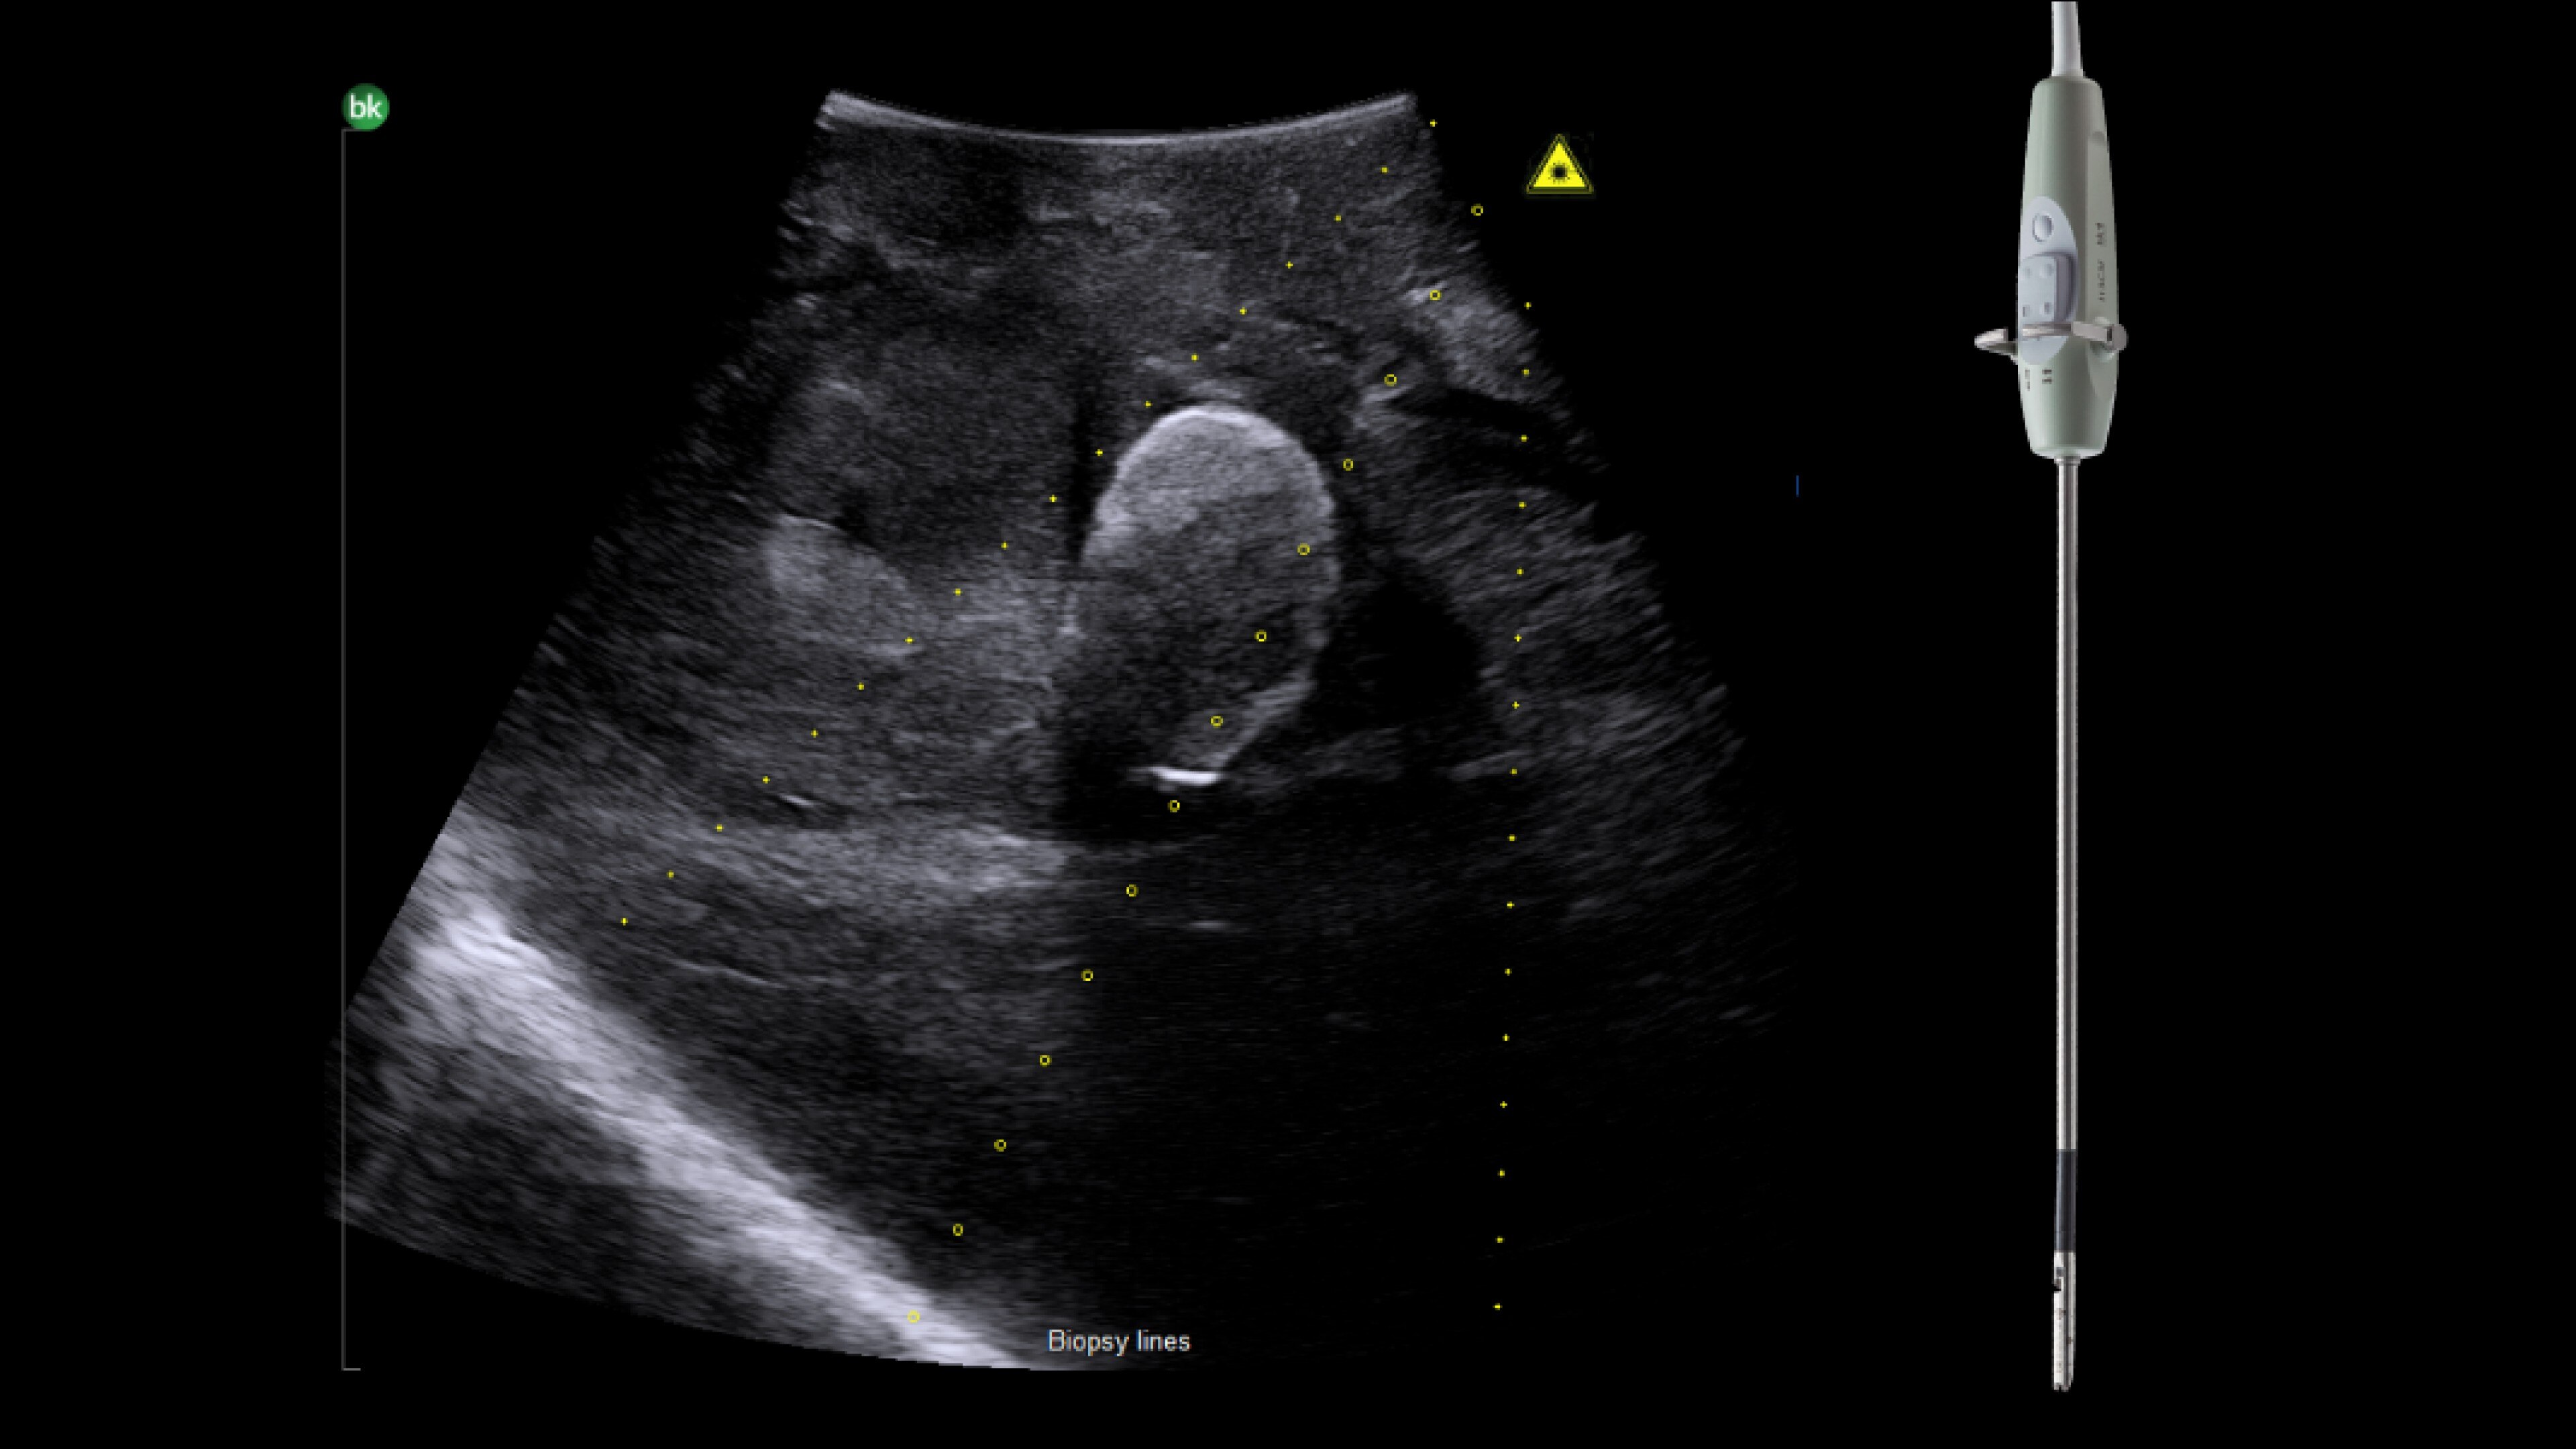

Ablation imaging

Active imaging supports liver and pancreas ablation procedures by helping you visualize lesions and blood vessels, identify healthy tissue vs. tumor, and guide and view needle placements.

Use intraoperative ultrasound to:

• Enable visualization of disease staging at the time of surgery with excellent image quality.

• Guide and view needle placements in real-time.

• Verify your planned results by assessing pre- and post-ablation images together.

Advanced Laparoscopic Transducer I13C3f*

• Plan and target tumor biopsies and ablations with patented laser technology.

• Achieve preferred insertion angle on up to two needles with proprietary channel design.